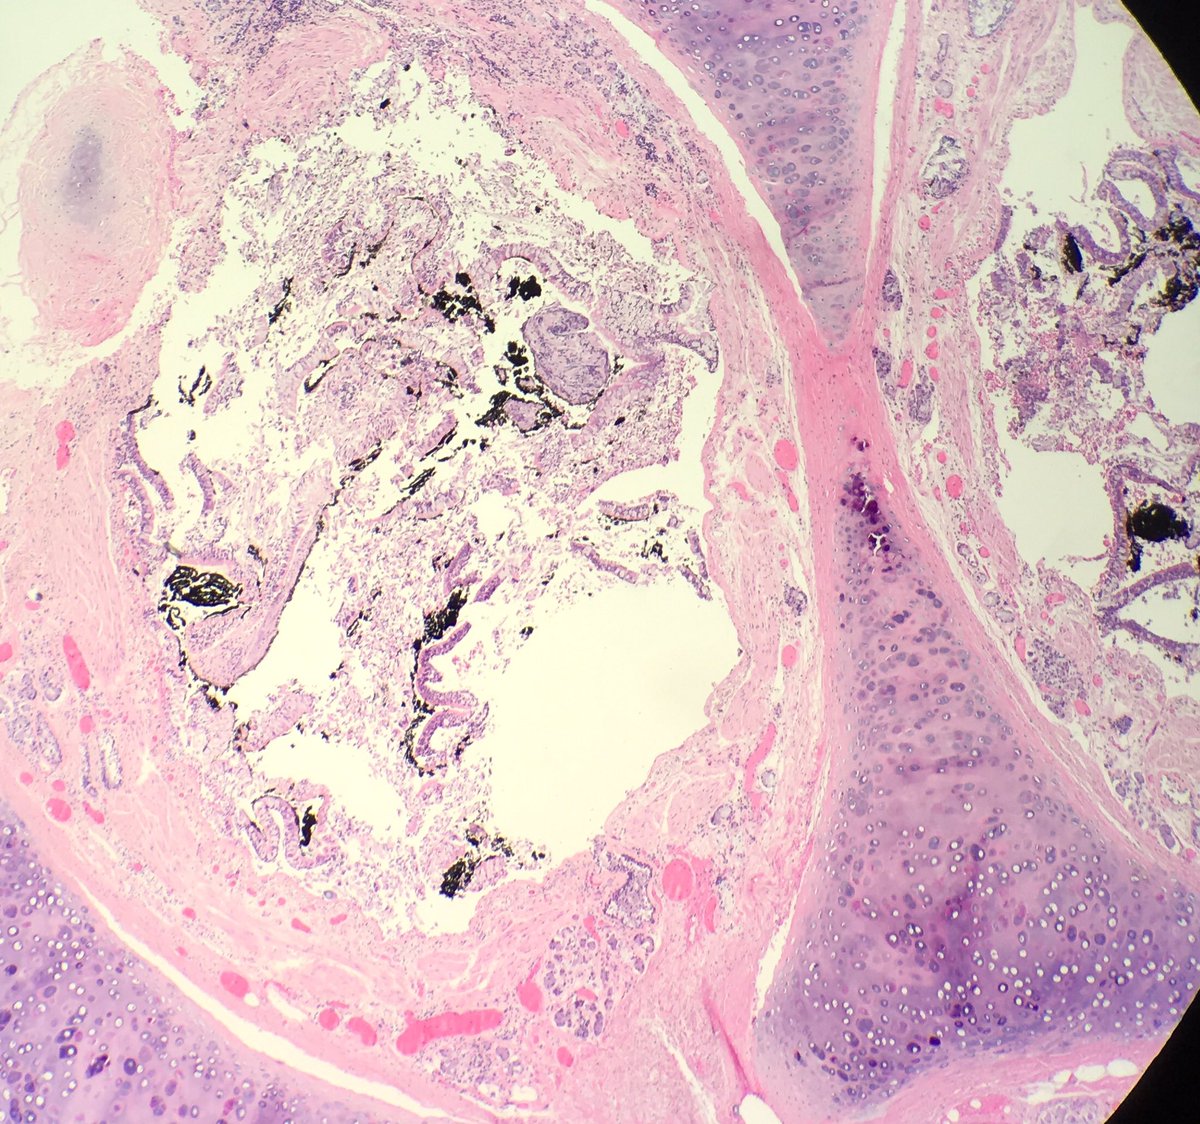

Fall from height: blunt force injuries including pulmonary contusions: interstitial and alveolar hemorrhage, damaged bronchioles and vessels with hemorrhage in the walls. Fat emboli can be seen (femoral shaft fracture x 2) #pulmonarypath #lungpath #forensics #forensicpath

seattlequinns's tweet image. Fall from height: blunt force injuries including pulmonary contusions: interstitial and alveolar hemorrhage, damaged bronchioles and vessels with hemorrhage in the walls. Fat emboli can be seen (femoral shaft fracture x 2) #pulmonarypath #lungpath #forensics #forensicpath